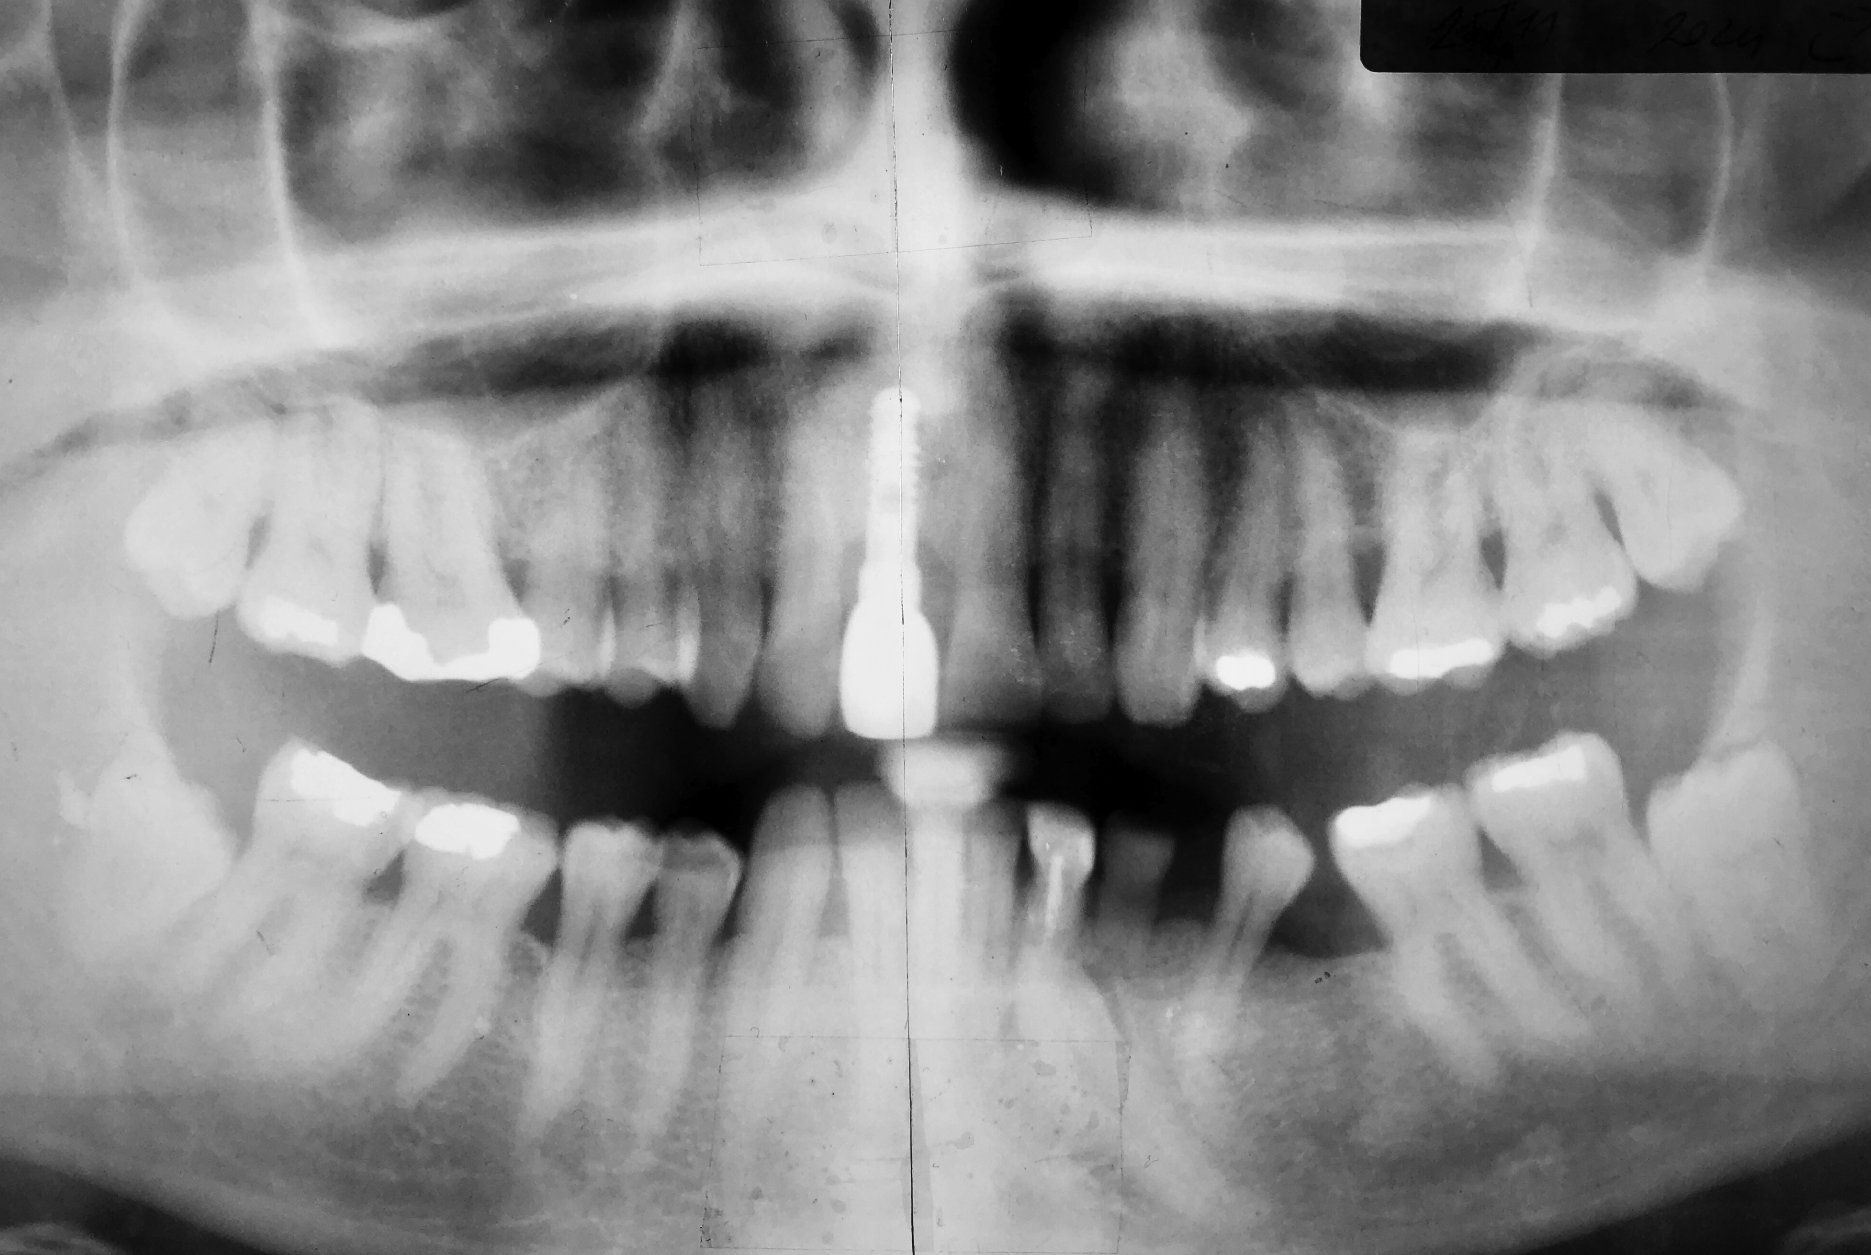

The most recent X-ray from November 2024. The implant has been functional for 23 years. Despite significant bruxism, the original dental restoration remains both functional and esthetically intact.